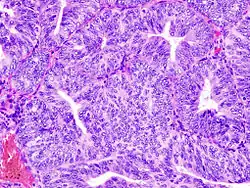

Anatomía patológica

La histopatología del cáncer endometrial es altamente diversa. El hallazgo más común es el adenocarcinoma endometrial bien diferenciado, el cual está compuesto por numerosas glándulas pequeñas, congestionadas con variados grados de atipia nuclear, actividad mitótica y estratificación. A menudo está situado en un fondo de hiperplasia endometrial. Los francos adenocarcinomas pueden distinguirse de la hiperplasia endometrial por el hallazgo de una clara invasión del estroma o por glándulas muy juntas (espalda-a-espalda) los cuales representan el reemplazo no destructivo del estroma endometrial por el cáncer. Con la progresión de la enfermedad, el miometrio llega a ser infiltrado.[11]